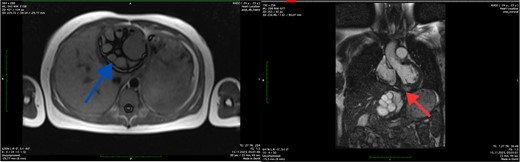

The MRI was conducted without contrast enhancement. Within the left ventricle, intramurally, specifically in the basal and medial segments (5, 6, 11, 12), a hyperintense MR signal was observed. These signals appeared round-oval in shape with clear, even contours and exhibited a heterogeneous structure due to internal partitions, measuring ~6.2 × 5.8 × 5.7 cm. The thoracic aorta displayed smooth contours, with a homogeneous MR signal reflecting the blood flow within its lumen. The trunk and branches of the pulmonary artery were identified and showed no signs of expansion. Additionally, in images captured in the left lobe of the liver, a multi-chamber formation was identified. This formation was round-oval in shape with smooth, clear contours and featured a thick capsule, measuring ~8.4 × 8.1 × 8.7 cm. The MRI findings indicated the presence of echinococcal cysts within the myocardium of the left ventricle and the left lobe of the liver (Fig. 2).

Axial MRI scan of the liver (blue arrow) and coronal MRI scan of the left ventricle (red arrow) showing the cystic lesions.